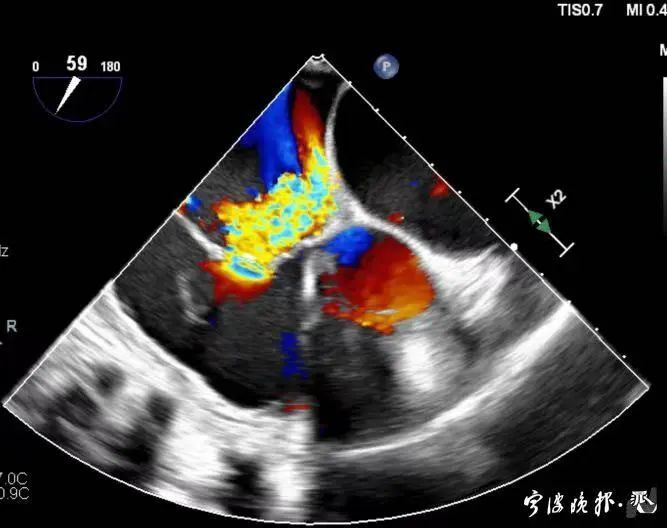

術前食道心超示三尖瓣重度反流